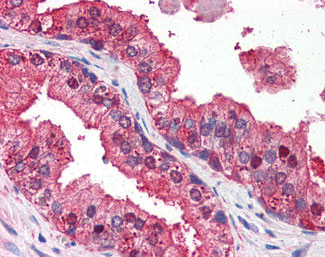

Anti-DRAM1 / DRAM antibody IHC of human prostate.